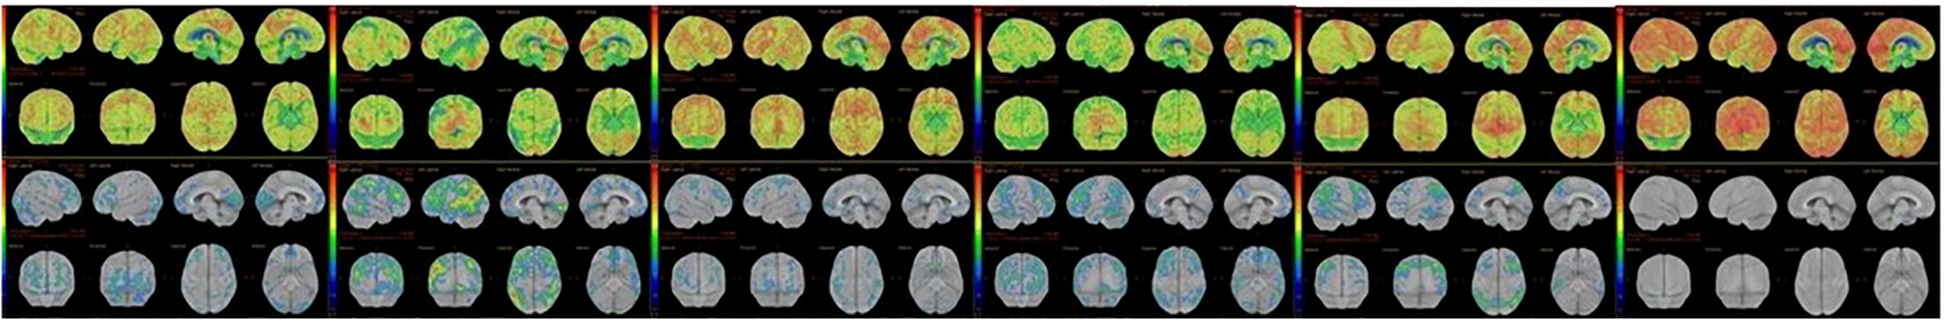

Diffuse EEG slowing was documented in 33.3% of HE patients (p=0.001). Structural MRI findings were nonspecific for limbic encephalitis and/or autoimmune encephalitis in the context of bilateral medial temporal hyperintensities in both cohorts. Fluorodeoxyglucose positron emission tomography (FDG-PET) revealed cortical hypometabolism in 85.7% of imaged HE patients (6/7), who underwent FDG-PET imaging, compared with 0% of imaged AD patients (0/5) (χ² = 10.500, p=0.001). FDG-PET images of six HE patients are shown in Figure 2. Additionally, two AD patients instead showed patterns suggestive of neurodegeneration, and both were subsequently diagnosed with neurodegenerative disease (N=2/7). Neuropsychiatric syndrome patterns and neurodiagnostic features in patients with the non-HE group and the HE group are shown in Table 2.

Figure 2

FDG-PET hypometabolism in six HE patients.

In the non-HE group initially suspected of HE (AD group), lorazepam and ECT effectively treated catatonia and other psychiatric symptoms; even those later diagnosed with neurodegenerative disease responded to ECT for their catatonic signs and symptoms. By discharge, Clinical Global Impression–Improvement scores did not differ between HE and primary psychiatric patients (1.44 ± 0.53 vs. 1.94 ± 0.96; U=102.0, p=0.190), reflecting substantial symptomatic recovery in both cohorts. In the HE group, MoCA scores improved from severely impaired (<10/30) to near-normal ranges (mid-20s to 30/30), and associated neurological signs, including parkinsonism, myoclonus, stroke-like features, dyskinesia, dysarthria, and language disorder, resolved in parallel. The FDG‐PET scans obtained during the remission phase following initial therapy for three patients are presented in Figure 3. Early control FDG‐PET studies performed after acute immunotherapy showed improvements in the pretreatment hypometabolism for these three patients. No follow-up FDG-PET data are available for other patients, as control scans were not performed. In those with baseline EEG abnormalities (N=3), follow‐up EEGs normalized. Notably, the subacute neurological motor symptoms listed in Table 4—Parkinsonism, myoclonus, dysarthria, language disorder, and stroke‐like episodes—resolved after 5–7 days of pulse therapy, concomitant with improvement in other neuropsychiatric manifestations. In the management of HE, following initial pulse corticosteroid therapy, immunotherapy was arranged as follows: two patients received maintenance treatment with oral steroids and azathioprine for nine months, one patient received maintenance oral steroids for six months, and the remaining patients received maintenance oral steroids for two months. Detailed objective treatment outcomes of patients with HE are shown in Table 5.

Figure 3

Treatment response in three patients with HE.